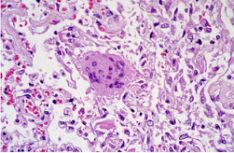

病理標(biāo)本的一種,制作時(shí)將部分有病變的組織或臟器經(jīng)過各種化學(xué)品和埋藏法的處理,使之固定硬化,在切片機(jī)上切成薄片,粘附在玻片上,染以各種顏色,供在顯微鏡下檢查,以觀察病理變化,作出病理診斷,為臨床診斷和治療提供幫助。

常用的染色方法是蘇木素-伊紅(Hematoxylin-Eosin)染色法,簡(jiǎn)稱H.E染色法。這種方法對(duì)任何固定液固定的組織和應(yīng)用各種包埋法的切片均可使用。蘇木素是一種堿性染料,可使組織中的嗜堿性物質(zhì)染成藍(lán)色,如細(xì)胞核中的染色質(zhì)等;伊紅是一種酸性染料,可使組織中的嗜酸性物質(zhì)染成紅色,如多數(shù)細(xì)胞的胞質(zhì)、核仁等在H.E染色的切片中均呈紅色。